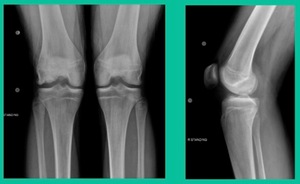

Now, we’ll shift to the adult. This is a 27-year-old. Right knee swelling, activity-related, and classic failed nonsurgical treatment on the lateral side of the knee.

This will probably be fixed. It’s a big piece and we’ll try to preserve it. The literature shows that preservation does pretty well. In this instance, there’s very little bone. It’s somewhat dystrophic, not very encouraging in my mind.

43-Year-Old, symptomatic medial femoral condyle.

D1 football player formally, affecting ADLs. For this one, I initially just wanted to watch it. This looks pretty small when he came in. Let’s see what happens. Six months later, this is where he progressed to.